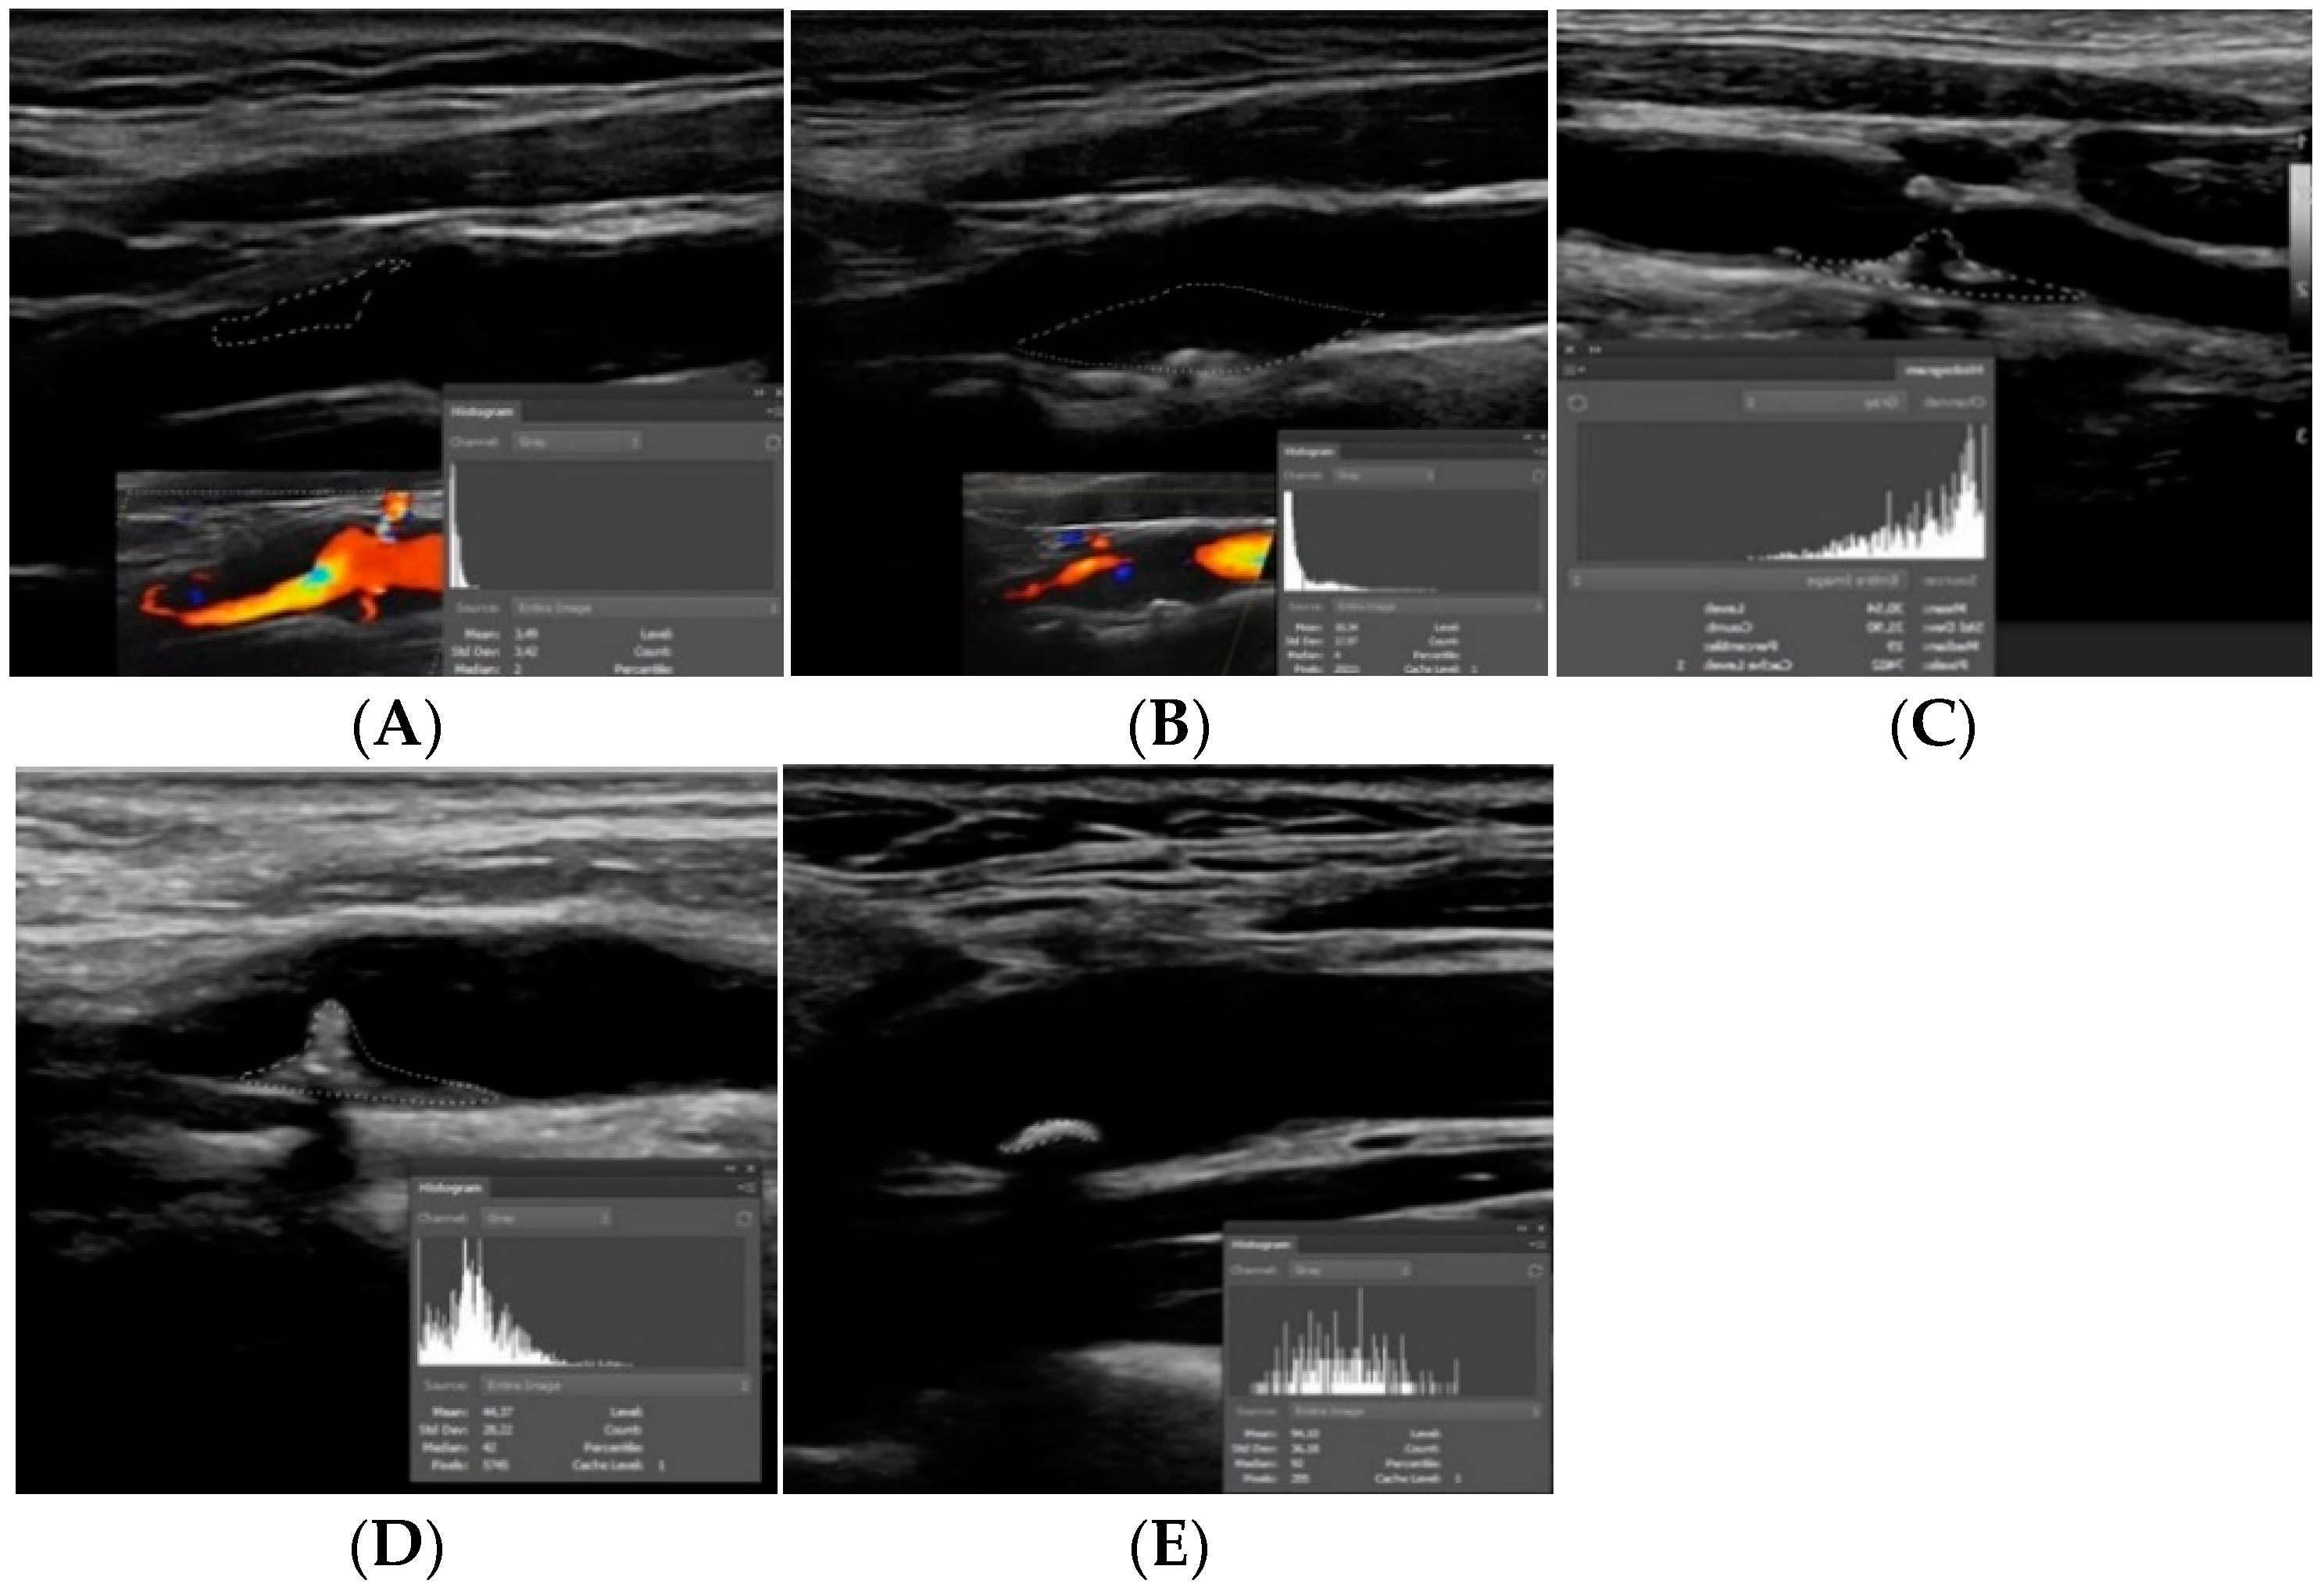

2. Plaque Echogenicity

- Sabetai, M.M.; Tegos, T.J.; Nicolaides, A.N.; Dhanjil, S.; Pare, G.J.; Stevens, J.M. Reproducibility of computer-quantified carotid plaque echogenicity: Can we overcome the subjectivity? Stroke 2000, 31, 2189–2196. [Google Scholar] [CrossRef]

- Wohlin, M.; Sundström, J.; Andrén, B.; Larsson, A.; Lind, L. An echolucent carotid artery intima-media complex is a new and independent predictor of mortality in an elderly male cohort. Atherosclerosis 2009, 205, 486–491. [Google Scholar] [CrossRef]

- Huang, Z.; Cheng, X.Q.; Liu, H.Y.; Bi, X.J.; Liu, Y.N.; Lv, W.Z.; Xiong, L.; Deng, Y.B. Relation of Carotid Plaque Features Detected with Ultrasonography-Based Radiomics to Clinical Symptoms. Transl. Stroke Res. 2021. [Google Scholar] [CrossRef] [PubMed]